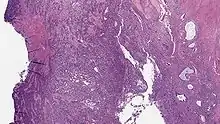

| Micrograph of a low-grade endometrial stromal sarcoma. H&E stain. | |

Low-grade endometrial stromal sarcoma

Low-grade endometrial stromal sarcoma consists of cells resembling normal proliferative phase endometrium, but with infiltration or vascular invasion. These behave less[3] aggressively, sometimes metastasizing, with cancer stage the best predictor of survival. The cells express estrogen/progesterone-receptors.

Microscopy

- Monotonous ovoid cells to spindly cells with minimal cytoplasm.

- Prominent arterioles. Angiolymphatic invasion common.

- Up to 10-15 mitotic figures per 10 HPF in most active areas.

- Tongue-like infiltration between muscle bundles of myometrium.

- May exhibit myxoid, epithelioid and fibrous change.

- May have foam cells or hyalinization in the stroma.